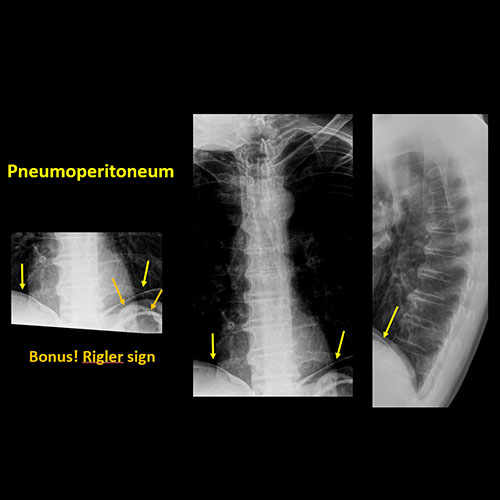

There is free intraperitoneal or retroperitoneal air, or other abnormal air in the included abdomen. |

No | NA |